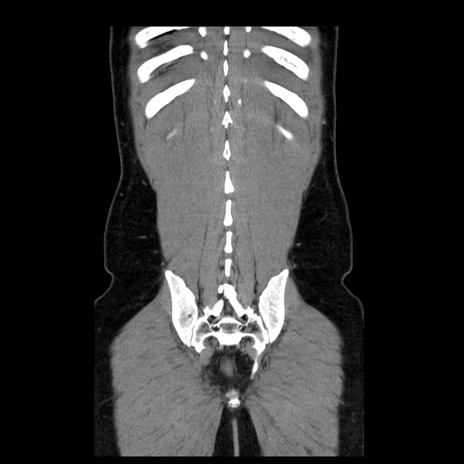

症例4(冠状断像)

【症例】30歳代男性

【主訴】腹痛、嘔吐

【現病歴】昨晩から突然の腹痛あり、その後嘔吐、軟便も出現。腹痛が改善しないため救急搬送となる。2日前にしめ鯖の食事歴あり。

【身体所見】意識清明、苦悶様、BP 135/90mmHg、BT 35.7℃、腹部:平坦、やや硬、心窩部〜臍部に自発痛、圧痛あり、筋性防御+、反跳痛-

【データ】WBC 8100、CRP 0.57